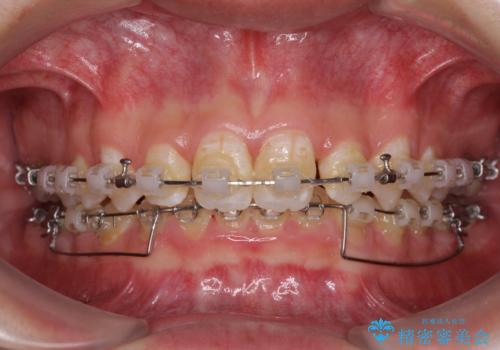

- クリアブラケット

前方に移動している上顎臼歯を補助装置にて遠心移動させることで1歯対2歯の臼歯咬合を目指し、同時に深い咬合を改善していくこととしました。

このような咬み合わせの場合、治療期間は2年以上がかかることが一般的で、3年程度かかることもありえるケースです。

強く深い咬み合わせにより下顎装置は頻繁に脱離するため、治療期間が長くなりますが、予定通りに終了させることができました。